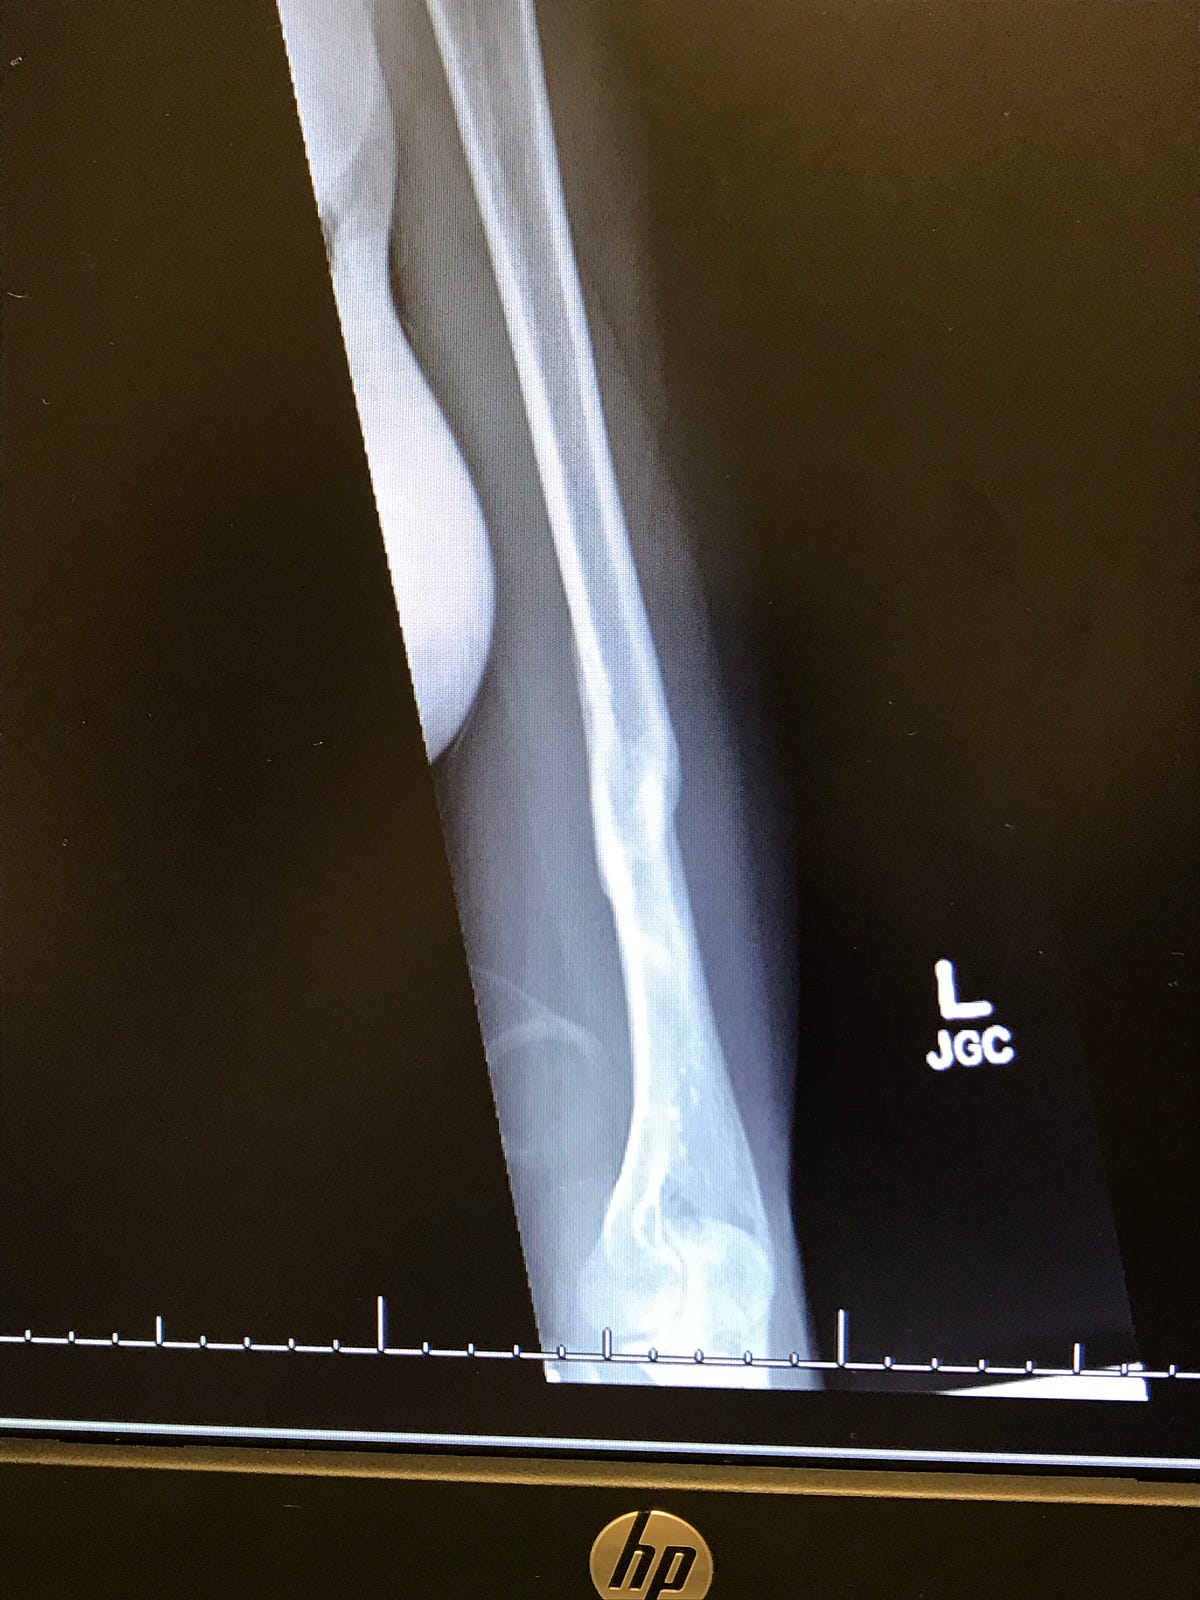

A Broken Humerus — Road to Recovery Maddie Wirthman Medium How To Shower With A Broken Humerus I recently fractured my left humerus and found that reading humerus fracture recovery blogs has been helpful in anticipating the healing process. There are two main approaches that your surgeon may use: During the first four weeks it is. In this video the surgeons discuss shoulder fractures. Shampoo and conditioner in basket at. They discuss the mechanism of injury, the.. How To Shower With A Broken Humerus.

A Broken Humerus — Road to Recovery by Maddie Wirthman Medium How To Shower With A Broken Humerus Wear the sling all the time, only removing it to regularly exercise your arm, and to shower. They discuss the mechanism of injury, the. Try to do this every 1 to 2 hours for the. Shampoo and conditioner in basket at. During the first four weeks it is. In this video the surgeons discuss shoulder fractures. If you have an. How To Shower With A Broken Humerus.